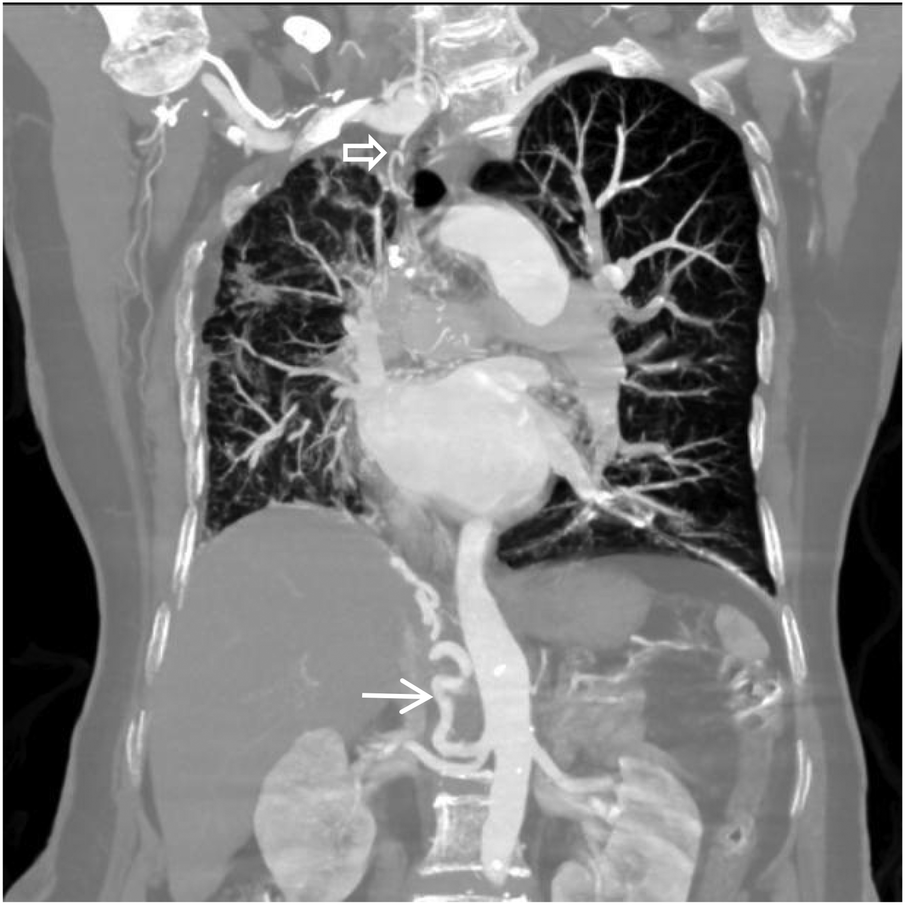

Figure 7

Coronal MIP image shows a large branch originating from the right renal artery entering the right lung (white arrow), and a branch of the right subclavian artery entering the right lung (empty arrow). Pulmonary arteries are not visible within the right lung.

Figure 8

Coronal MIP image shows marked enlargement and tortuosity of the origins of the intercostal arteries on the right side of the thoracic aorta (white arrow).

Thoracoabdominal aortic CTA and chest CT findings are illustrated in Figures 1–14. There was no evidence of aortic dissection. The right pulmonary artery was absent distal to approximately 3 cm from the bifurcation, with a smooth and rounded defect margin. The main pulmonary artery and its major branches showed no abnormal densities. No right pulmonary artery branches were observed in the right lung. Multiple tortuous arterial branches from the right subclavian artery, descending aorta, and right renal artery supplied the right lung. The right hemithorax was smaller, with localized pleural thickening and adhesions bilaterally. Multiple bronchiectasis with thickened walls and patchy, nodular, and linear opacities encircled the right lung. Increased translucency and several hyperlucent regions were visible in the left lung. CT imaging findings demonstrated: 1. Congenital absence of the right pulmonary artery (RPA), with the right lung supplied by collateral circulation originating from the right subclavian artery, right intercostal arteries, and the right renal artery. 2. Right pulmonary hypoplasia, bronchiectasis of the right lung, accompanied by infection and partial consolidation in the right upper lobe, compensatory hyperinflation of the left lung, and multiple bullae in the left lung. 3. Bilateral localized pleural thickening and adhesions. 4. Osteoporosis and mild flattening of the T6 vertebra and compression fractures of T11 and T12.

Unilateral absence of the pulmonary artery (UAPA), or unilateral pulmonary artery agenesis, is a rare congenital condition caused by developmental malformation of the pulmonary vasculature. The condition often occurs together with congenital heart diseases, including atrial septal defect and tetralogy of Fallot. However, when it occurs without any other congenital heart defects, it is referred to as IUAPA, which is even rarer. Based on the data presented by Bouros et al. (2), the incidence of the condition is approximately 1 in 200,000, often presenting with right-sided predominance. However, relevant data from Chinese statistics is limited. Digital subtraction angiography (DSA) pulmonary angiography remains the gold standard for diagnosing IUAPA. A review of the existing relevant literature indicates that a significant proportion of reported cases have come from the discipline of ultrasound medicine in China (3, 4). However, CTA has gradually gained significance as a clinical examination technique in recent years. This is mainly due to the greater accessibility of CT equipment in comparison to DSA and its numerous advantages, which include rapid and easy application, minimal invasiveness, and its ability to simultaneously assess extravascular pathology (5). Using DSA or CT pulmonary angiography, the imaging typically reveals that the proximal segment of the affected pulmonary artery terminates in a smooth, rounded blind end, with non-opacified pulmonary trunk and distal branches. Due to the single functioning pulmonary artery, the main and contralateral pulmonary artery may appear dilated and tortuous. Extensive systematic collateral arteries develop from the systemic circulation, branching from vessels such as the aorta, intercostal artery, bronchial artery, subclavian artery, internal thoracic artery, internal mammary artery, phrenic artery, renal artery or coronary artery to supply the affected area. Aortic angiography is often used to visualize these systemic-to-pulmonary connections. In the presented case, the thoracic and abdominal aortic CTA clearly demonstrated the absence of the distal right pulmonary artery and the presence of a prominent collateral supply to the right lung from branches of bronchial artery, the right renal artery, right intercostal arteries, and right subclavian artery. Chest CT typically reveals a loss of volume in the affected lung, a shift in the trachea and mediastinum towards the affected side, asymmetric bronchovascular markings, and frequently, dilation of the contralateral pulmonary artery. It is also commonly accompanied by findings such as ipsilateral pneumonia, partial atelectasis, bronchiectasis, heterogeneous emphysema, and pulmonary bullae. The chest CT findings in this case are consistent with this description. During embryogenesis, the pathoanatomical features of UAPA include the development of the main pulmonary artery and the proximal segments of the right and left pulmonary arteries from the ventral portion of the sixth aortic arch. Conversely, the intrapulmonary arteries and their branches originate from the postbranchial pulmonary vascular plexus. If the central pulmonary artery is not fully developed or there is localized obliteration, leading to an inability to form the usual connections and communications with the intrapulmonary arteries, a congenital vascular malformation characterized by the absence of one or both pulmonary arteries is indicated. In the absence of one pulmonary artery, the affected lung is deprived of the blood flow necessary for its pulmonary circulation, which is a part of the dual pulmonary blood supply. Consequently, the affected lung is sustained by bronchial arteries or other systemic collateral vessels for perfusion, resulting in a poorer blood supply compared to the contralateral lung. This has severe consequences for pulmonary development, resulting in pulmonary hypoplasia and volume loss in the affected lung. In addition, hypocapnia develops in the alveoli and respiratory bronchioles as the affected lung's main blood supply comes from systemic arteries that have a low carbon dioxide content. Research has shown that this condition can lead to the triggering of bronchospasm, the reduction of pulmonary ventilation, the impairment of mucociliary clearance in the bronchial walls, and the subsequent occurrence of recurrent respiratory infections. It has been established that hypoventilation and hypoxia in the affected lung can induce pulmonary vascular wall thickening, vasoconstriction, and ultimately lead to pulmonary hypertension(PH) and even right heart failure. PH resulting from UAPA is classified as a form of “segmental pulmonary hypertension”, with a reported incidence ranging from 19% to 44%. Segmental pulmonary hypertension currently refers to a condition where diverse sources of pulmonary blood supply lead to distal pulmonary vascular disease, variably affecting different lung segments (6, 7). The collateral vessels supplying the affected lung are often dysplastic and prone to causing symptoms such as hemoptysis. The cumulative impact of these pulmonary pathologies leads to a variety of clinical and imaging presentations that resemble bronchiectasis, pulmonary tuberculosis, COPD, and pulmonary embolism, none of which are specific. This results in the prolonged misdiagnosis of the majority of patients with these prevalent diseases (8–10). The patient had received treatment for 30 years for diagnoses of pulmonary tuberculosis and COPD, with suboptimal therapeutic outcomes. During this period, multiple chest CT scans were performed; however, a comprehensive assessment of the pulmonary vascular system was not conducted, nor was the potential relationship between the long-standing recurrent pulmonary pathologies and pulmonary vascular developmental abnormalities considered. Instead, the absence of RPA was incidentally identified during CTA performed to investigate the cause of chest pain, with multiple systemic collateral vessels observed supplying the right lung. Concurrent echocardiography revealed no definite intracardiac structural abnormalities. Following a thorough review of the available evidence, the initial diagnoses were found to be consistent with the condition known as IUAPA. Hemoptysis is one of the primary clinical symptoms associated with this particular disease. Combined with chest pain and shortness of breath caused by pulmonary pathology, the clinical picture can resemble pulmonary embolism. Therefore, this disease should be differentiated from pulmonary embolism clinically. Acute pulmonary embolism often shows a significant elevation in plasma D-dimer levels. Although this patient had chest pain, it was ultimately confirmed to be caused by an osteoporotic vertebral compression fracture, involving an element of chance.Current management of this condition primarily focuses on symptomatic treatment, mainly aimed at preventing hemoptysis, infection, and PH. Early intervention in infants and young children through pulmonary revascularization of the affected lung may facilitate normal pulmonary development and reduce adverse outcomes such as PH.